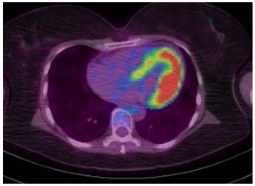

| Imaging Modality | Imaging Illustrations | Description |

|---|---|---|

| Cardiac MRI | ![]() | Short-axis view reveal interventricular mid-myocardial LGE (black arrow). |